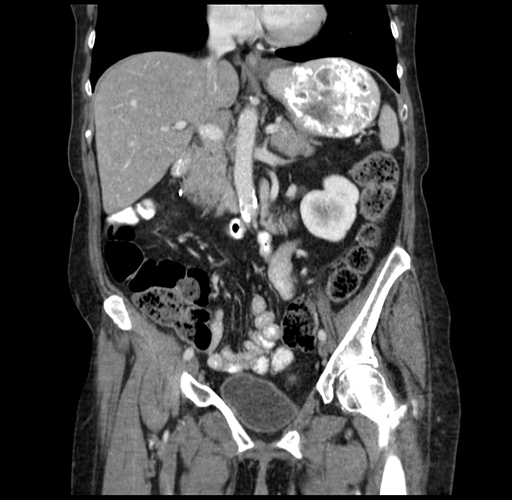

Pre-Chemo: Coronal Venous